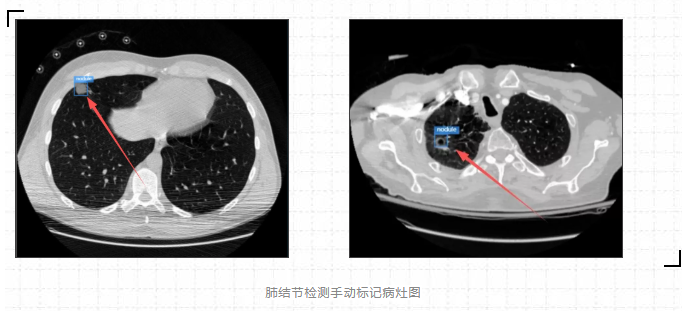

进入到测试界面,单击“上传”图片,进行检测:

箭头指的地方可看见检测结果,可以说利用ModelArts平台训练出来的肺结节检测模型检测效果是很棒的。(直接看太小的话,可以点开图片放大看)

从最后实验的结果对比图来看,可以说利用ModelArts平台训练出来的肺结节检测模型检测效果是很棒的,虽然存在一定的肺结节病灶假阳性标记,但是这在小样本数据集的人工智能医疗检测中是会出现的情况。毕竟对于人工智能医疗检测模型来说,只用了300张标注图片就能达到这样的效果,真的让人感到惊喜。